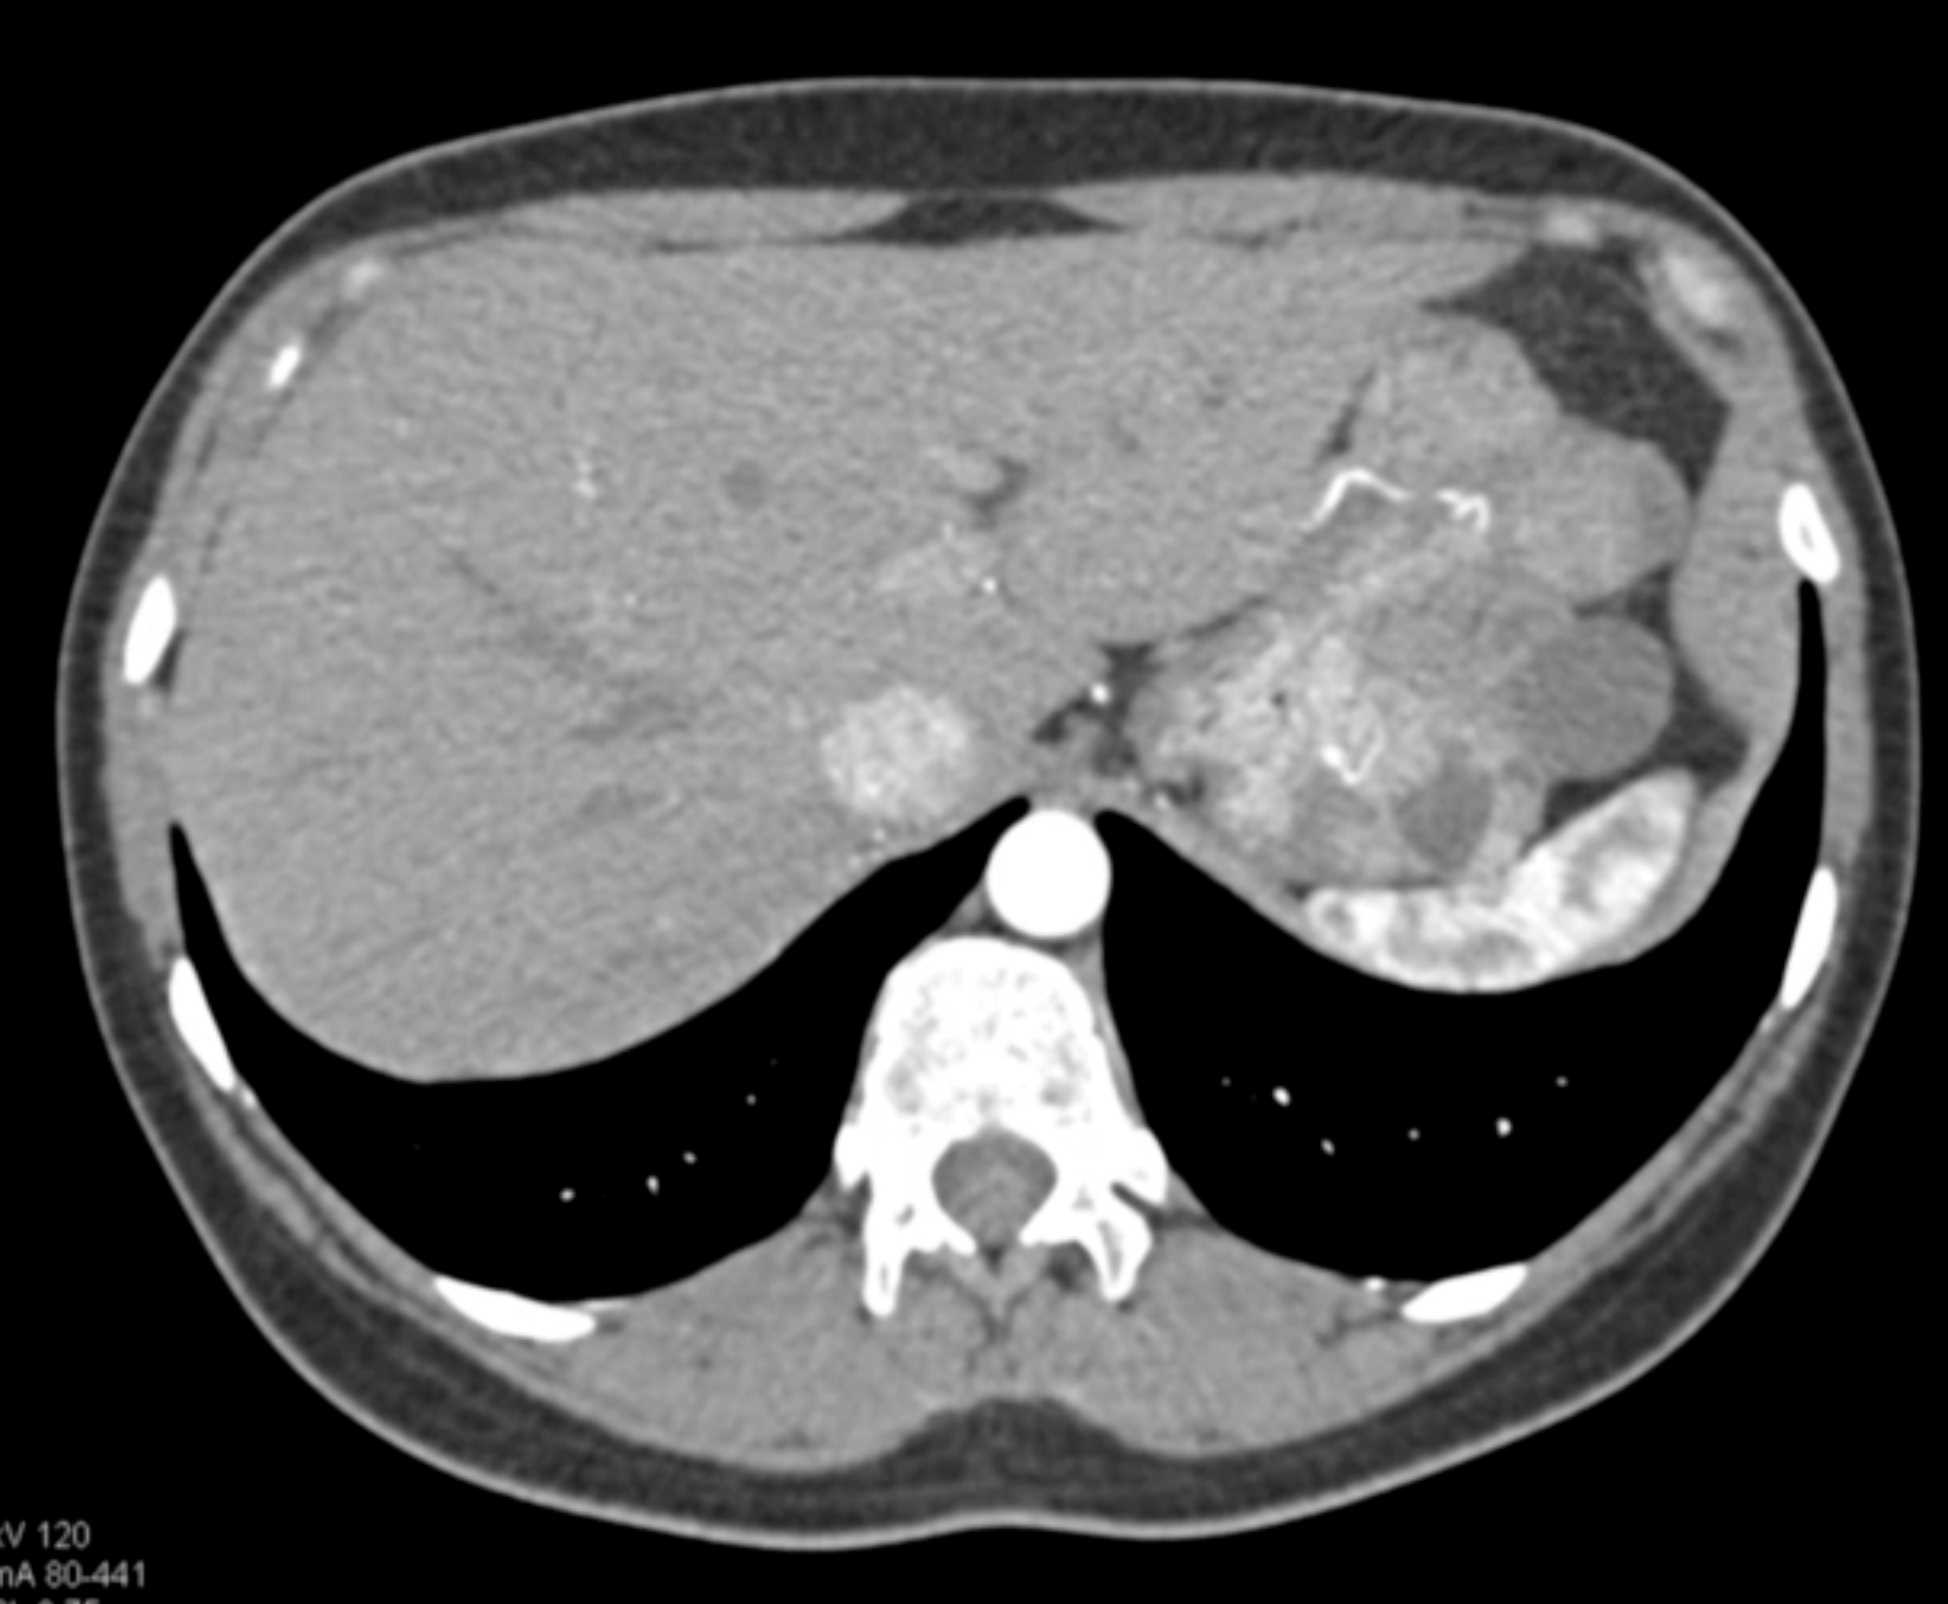

Multiple Gastric GIST Tumors with Spread to Nodes (Carney-Stratakis Syndrome)